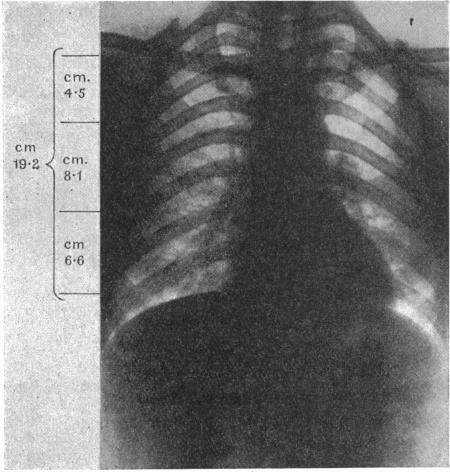

The Mechanostructure of the Pericardium.

J Anat. 1932 Oct;67(Pt 1):78-107.